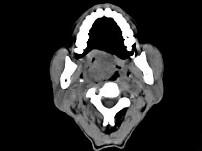

问题 男性,57岁,睡觉打鼾,近来加重,CT扫描如图所示,请选择正确的描述和答案()

选项 A.鼻咽腔偏右侧可见类圆形软组织块影 B.肿块内密度尚均匀,其上方见较多钙化影 C.肿块边缘大部清楚,邻近结构未见明显受侵 D.考虑为鼻咽癌 E.考虑为鼻咽部多形性腺瘤

答案 ABCE